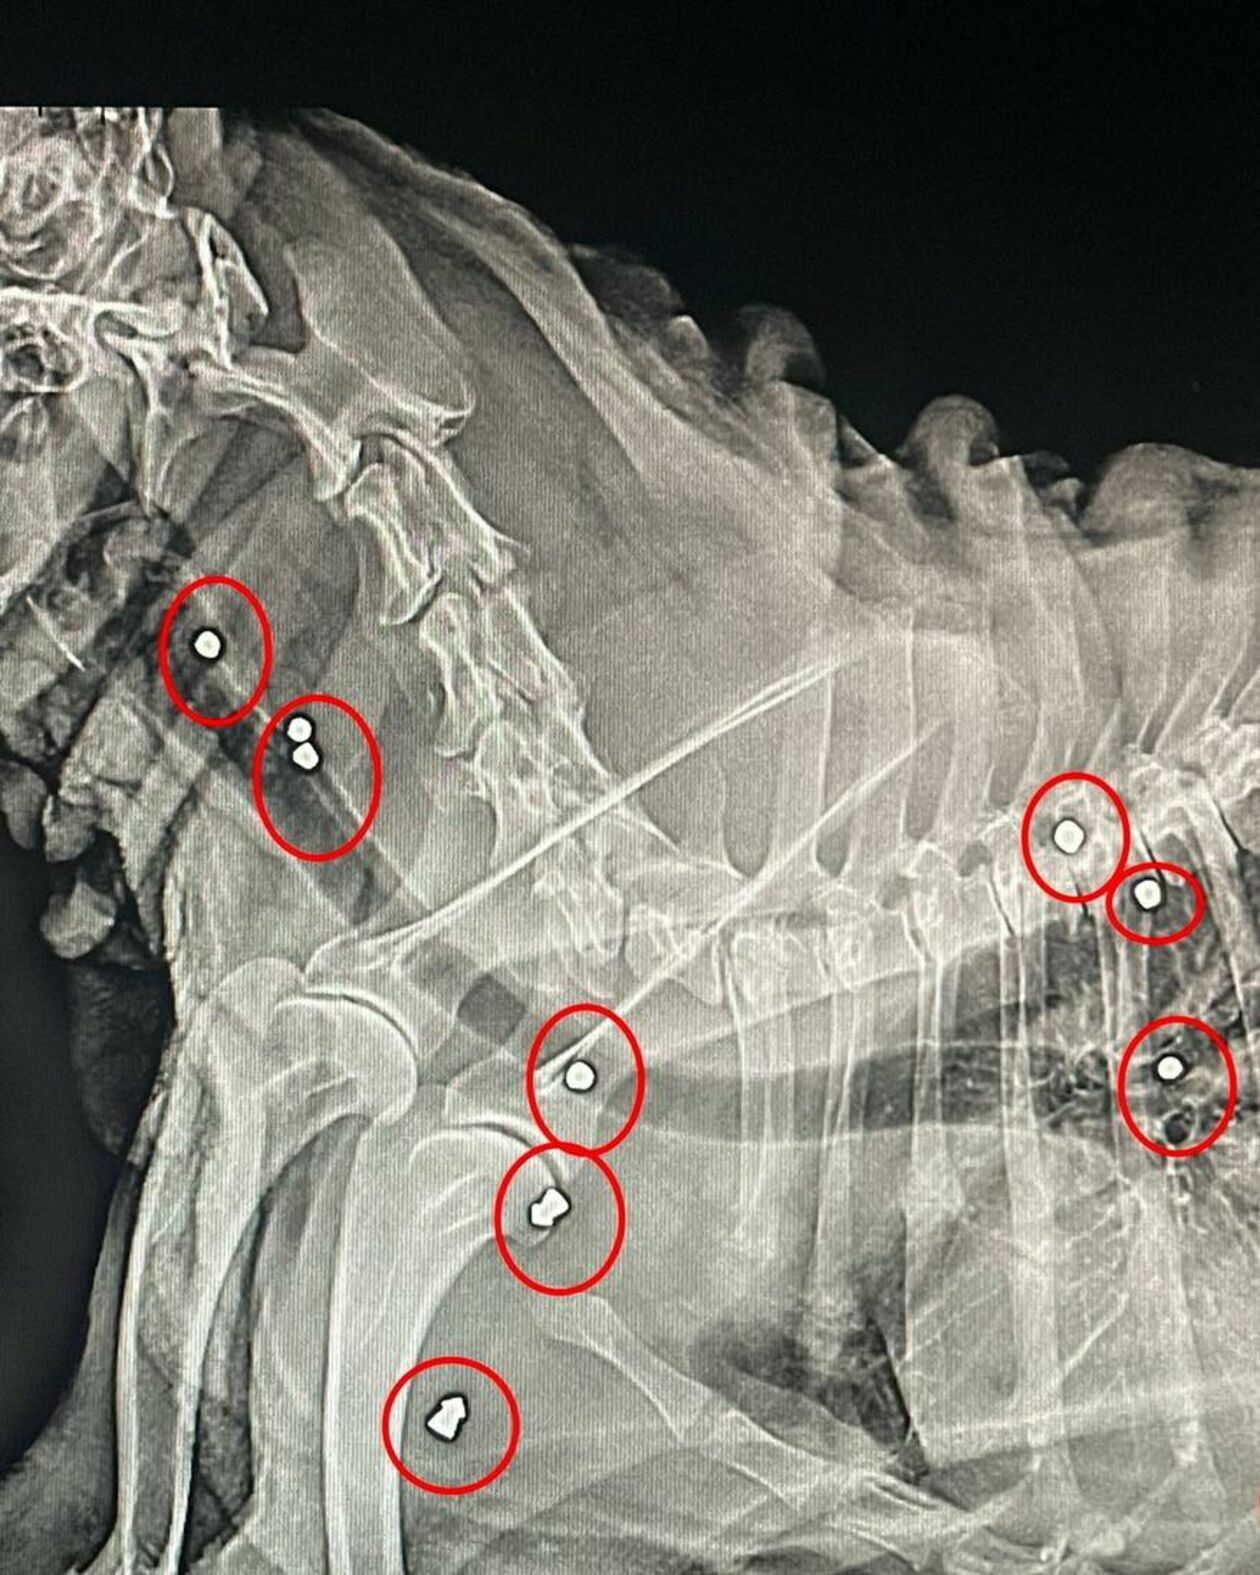

Jednak ogrom cierpienia, którego doznał pies, wyszedł na jaw dopiero wtedy, gdy w lecznicy zrobiono mu prześwietlenie. Okazało się, że do psa ktoś wielokrotnie strzelał.

Po całym ciele Begiera rozproszone są kawałki śrutu. Lekarze nie będą go wyjmować, bo zabieg byłby zbyt ryzykowny. – Mógłby mu bardziej zaszkodzić niż pomóc – wyjaśnia Włosek.